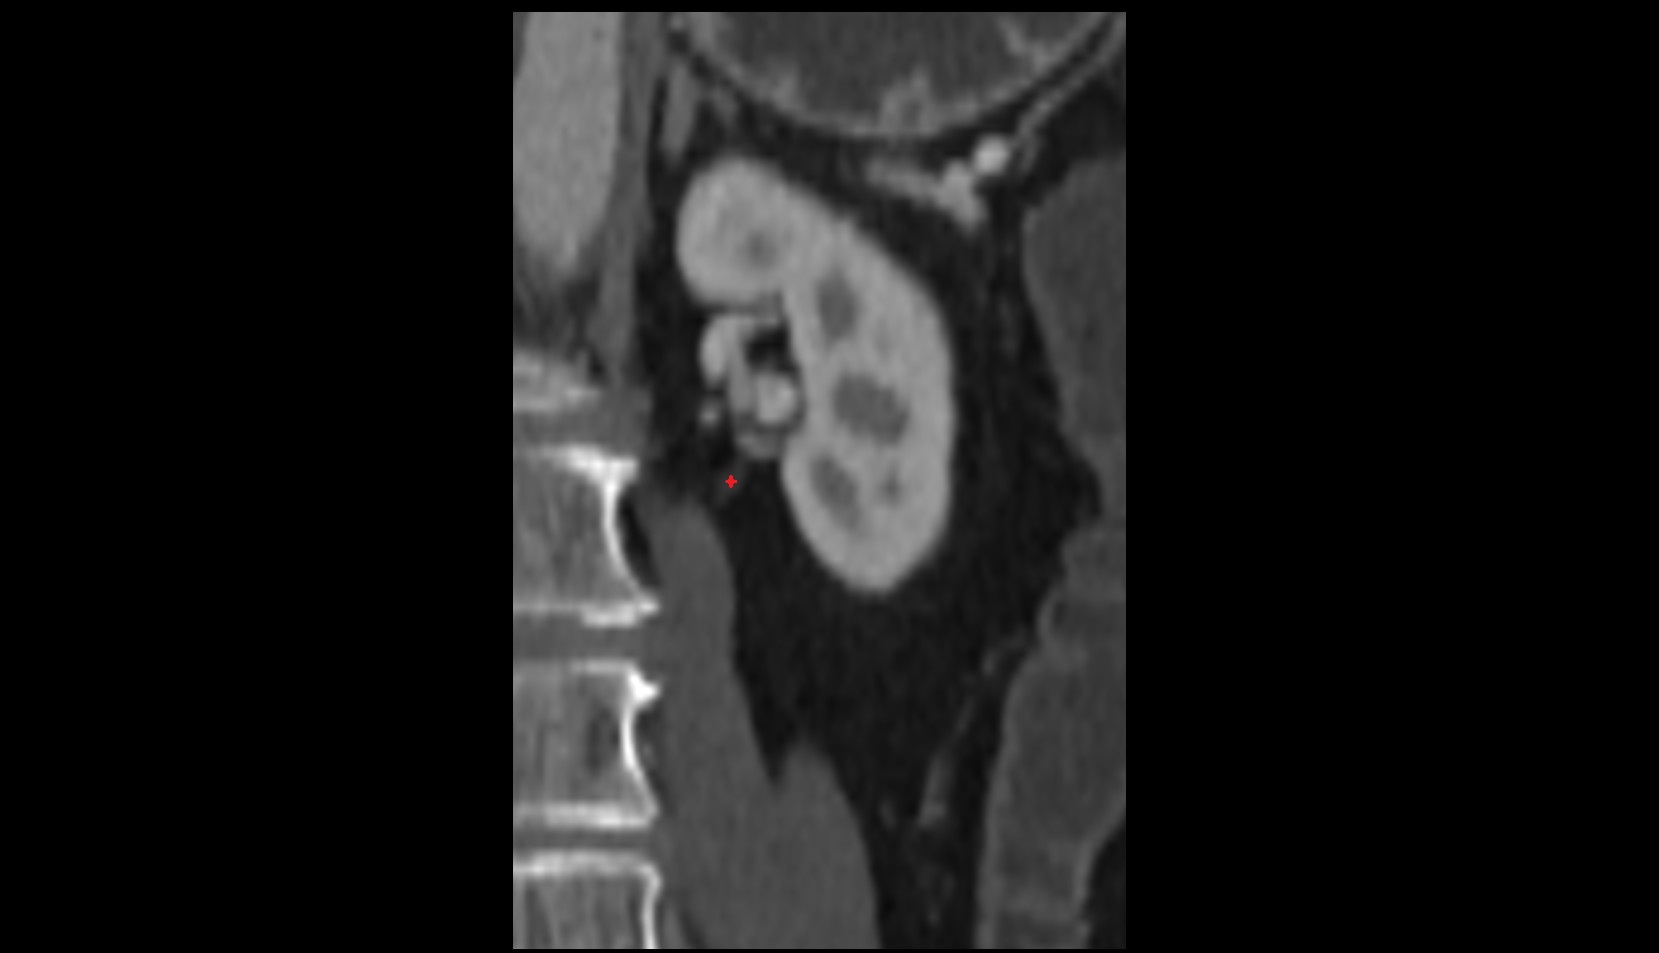

- kidneys

- Right kidney

- Left kidney

- Kidney cortex (Renal cortex)

- Renal medulla

- Renal pyramids

- Renal artery

- Renal vein